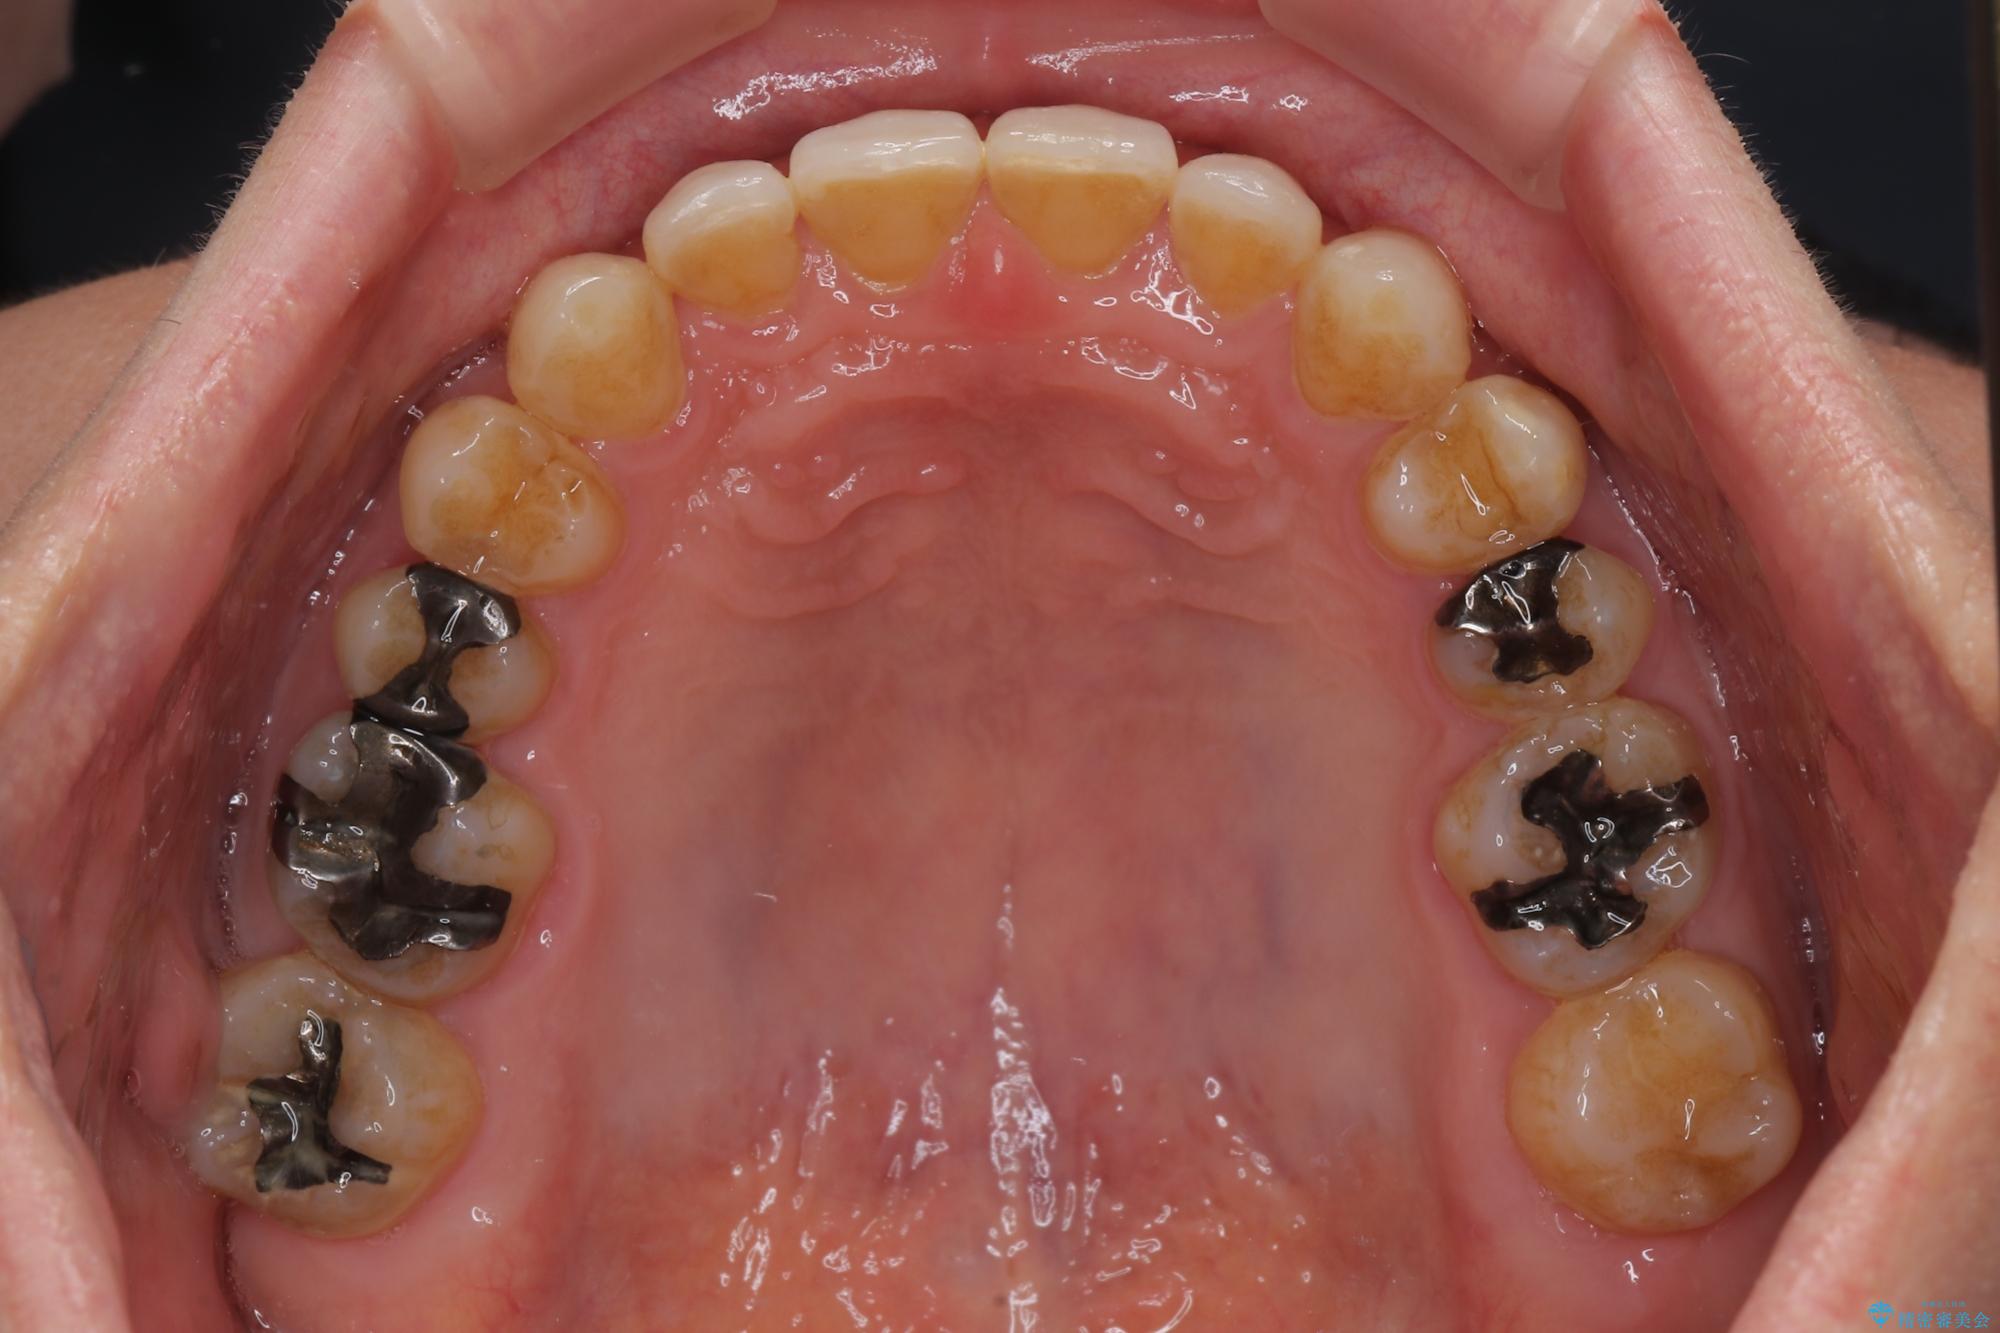

下顎前歯が隠れるほどのディープバイトにより、強い咬合力と突き上げで上顎歯列に隙間が空いている状態でした。

手前に傾斜している奥歯をワイヤー装置で立ち上がらせ、咬み合わせの高さを挙上することで突き上げを解消し、空隙歯列を改善していくこととしました。